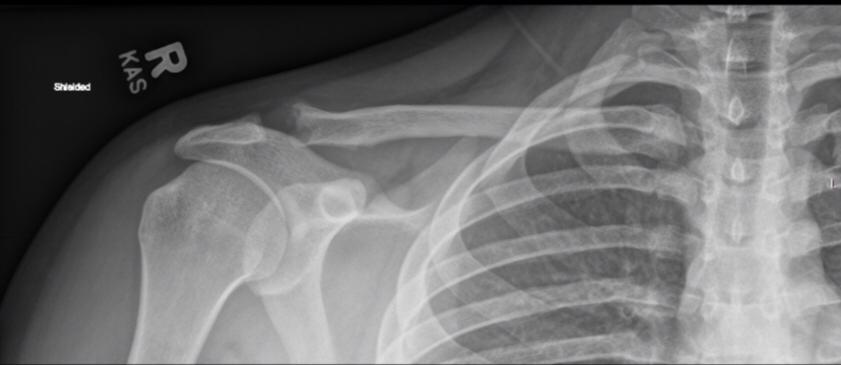

Distal clavicle osteolysis is a unique disease most likely due to an overuse phenomenon. Distal clavicular osteolysis (DCO) follows both chronic repetitive stress and single acromioclavicular trauma. Acute distal clavicular osteolysis was first described in 1936.

The exact aetiopathogenesis is unclear, but AC-joint trauma and subchondral microfractures seem to be involved. Subsequent attempts at repair are insufficient and the final result is osteolysis. It is unclear why changes predominate in the distal clavicle while the acromion is relatively spared.)

Mostly affected males in their 20s and commonly seen in weightlifters, symptoms usually begin with an insidious aching pain in the AC region that is exacerbated by weight training. Clinical findings are often nonspecific and frequently overlap with those of labral or rotator cuff tears. On examination, patients have point tenderness over the affected AC joint and pain with a cross-body adduction maneuver.

Conventional radiographs may remain normal during the first months or years. A 15° cephalad inclination avoids superposition of the scapular spine with the AC-joint (Zanca view).

Radiographic changes include cortical thinning, irregularity and microcysts in distal clavicle and mild AC–joint widening. A late finding is tapering of the distal clavicle.

MRI is far more sensitive to detect DCO in an early stage. The most common MR-finding is bone marrow oedema in the distal clavicle, sometimes also in the articular part of the acromion, but less distinct.

Often, a hypointense line is seen in this area of clavicular bone marrow oedema, representing a subchondral fracture. AC-joint abnormalities are common, and include effusion, mild widening, intra-articular bone fragments and capsule hypertrophy. Other MR-findings are similar to those seen on radiographs, as described above.

Bone scan may also shows increased uptake in the distal clavicle, which could be seen earlier than radiographic changes.

Treatment is essentially conservative, consisting of rest and nonsteroidal anti-inflammatory drugs (NSAID's), and is usually successful. In severe cases, resection of the distal clavicle is indicated. If left untreated, the process may cause progressive resorption of lateral aspect of the clavicle, erosions and cupping of the acromion and dystrophic calcifications.

DCO should be considered in the differential diagnosis of shoulder pain in the appropriate population. Therefore, analysis of MR arthrographic studies of the shoulder should not be restricted to evaluation of the rotator cuff and capsulolabral system, but the AC-joint should be scrutinised as well.